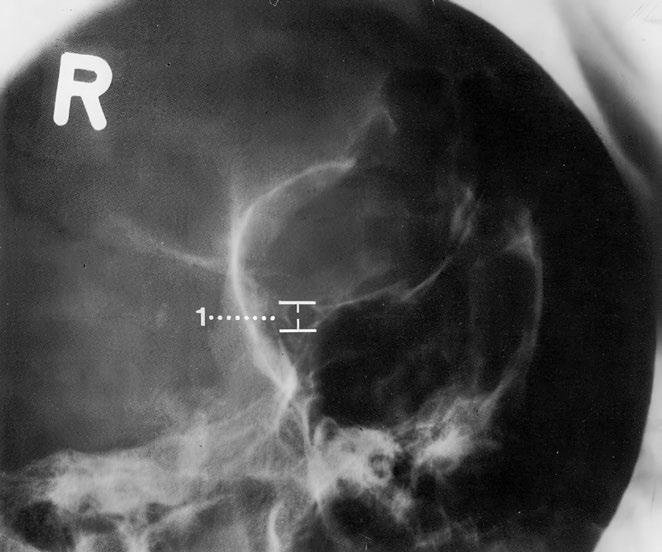

Rameno dolní čelisti

Zobrazený úsek dolní čelisti je svým tvarem a velikostí normální Čelistní úhel náležitý Mineralizace a kostní struktura jsou normální Hladké a ostré kontury normálně široké kortikalis bez patologických přerušení kontinuity

Normální tvar a postavení kostěných částí podílejících se na čelistním kloubu, hladké kontury Stav chrupu nenápadný, sanovaný Bez známek kalcifikací měkkých tkání nebo rentgenkontrastních cizích těles

Závěr

Normální zobrazení ramena dolní čelisti a čelistního kloubu

Kontrolní seznam

Tvar – šířka (hypertrofie, atrofie)

– čelistní úhel (viz níže)

– konfigurace processus condylaris a muscularis mandibulae

Struktura – mineralizace

– spongióza pravidelně uspořádaná a ostře ohraničená

– bez zhutnění, projasnění (podél kořenů zubů, např bublinkovitá)

– parodontální štěrbiny nejsou rozšířené

Kontury – intaktní

– hladké a ostré ohraničení

– bez ohraničených rozšíření nebo ztenčení

– canalis mandibulae: průběh, kontura (schody?)

Kloub

– kontura kloubní hlavice hladká

– artikulace v jamce

– tuberculum articulare: tvar, kontura (hladká)

Důležité údaje (1) Čelistní úhel asi 110–140°